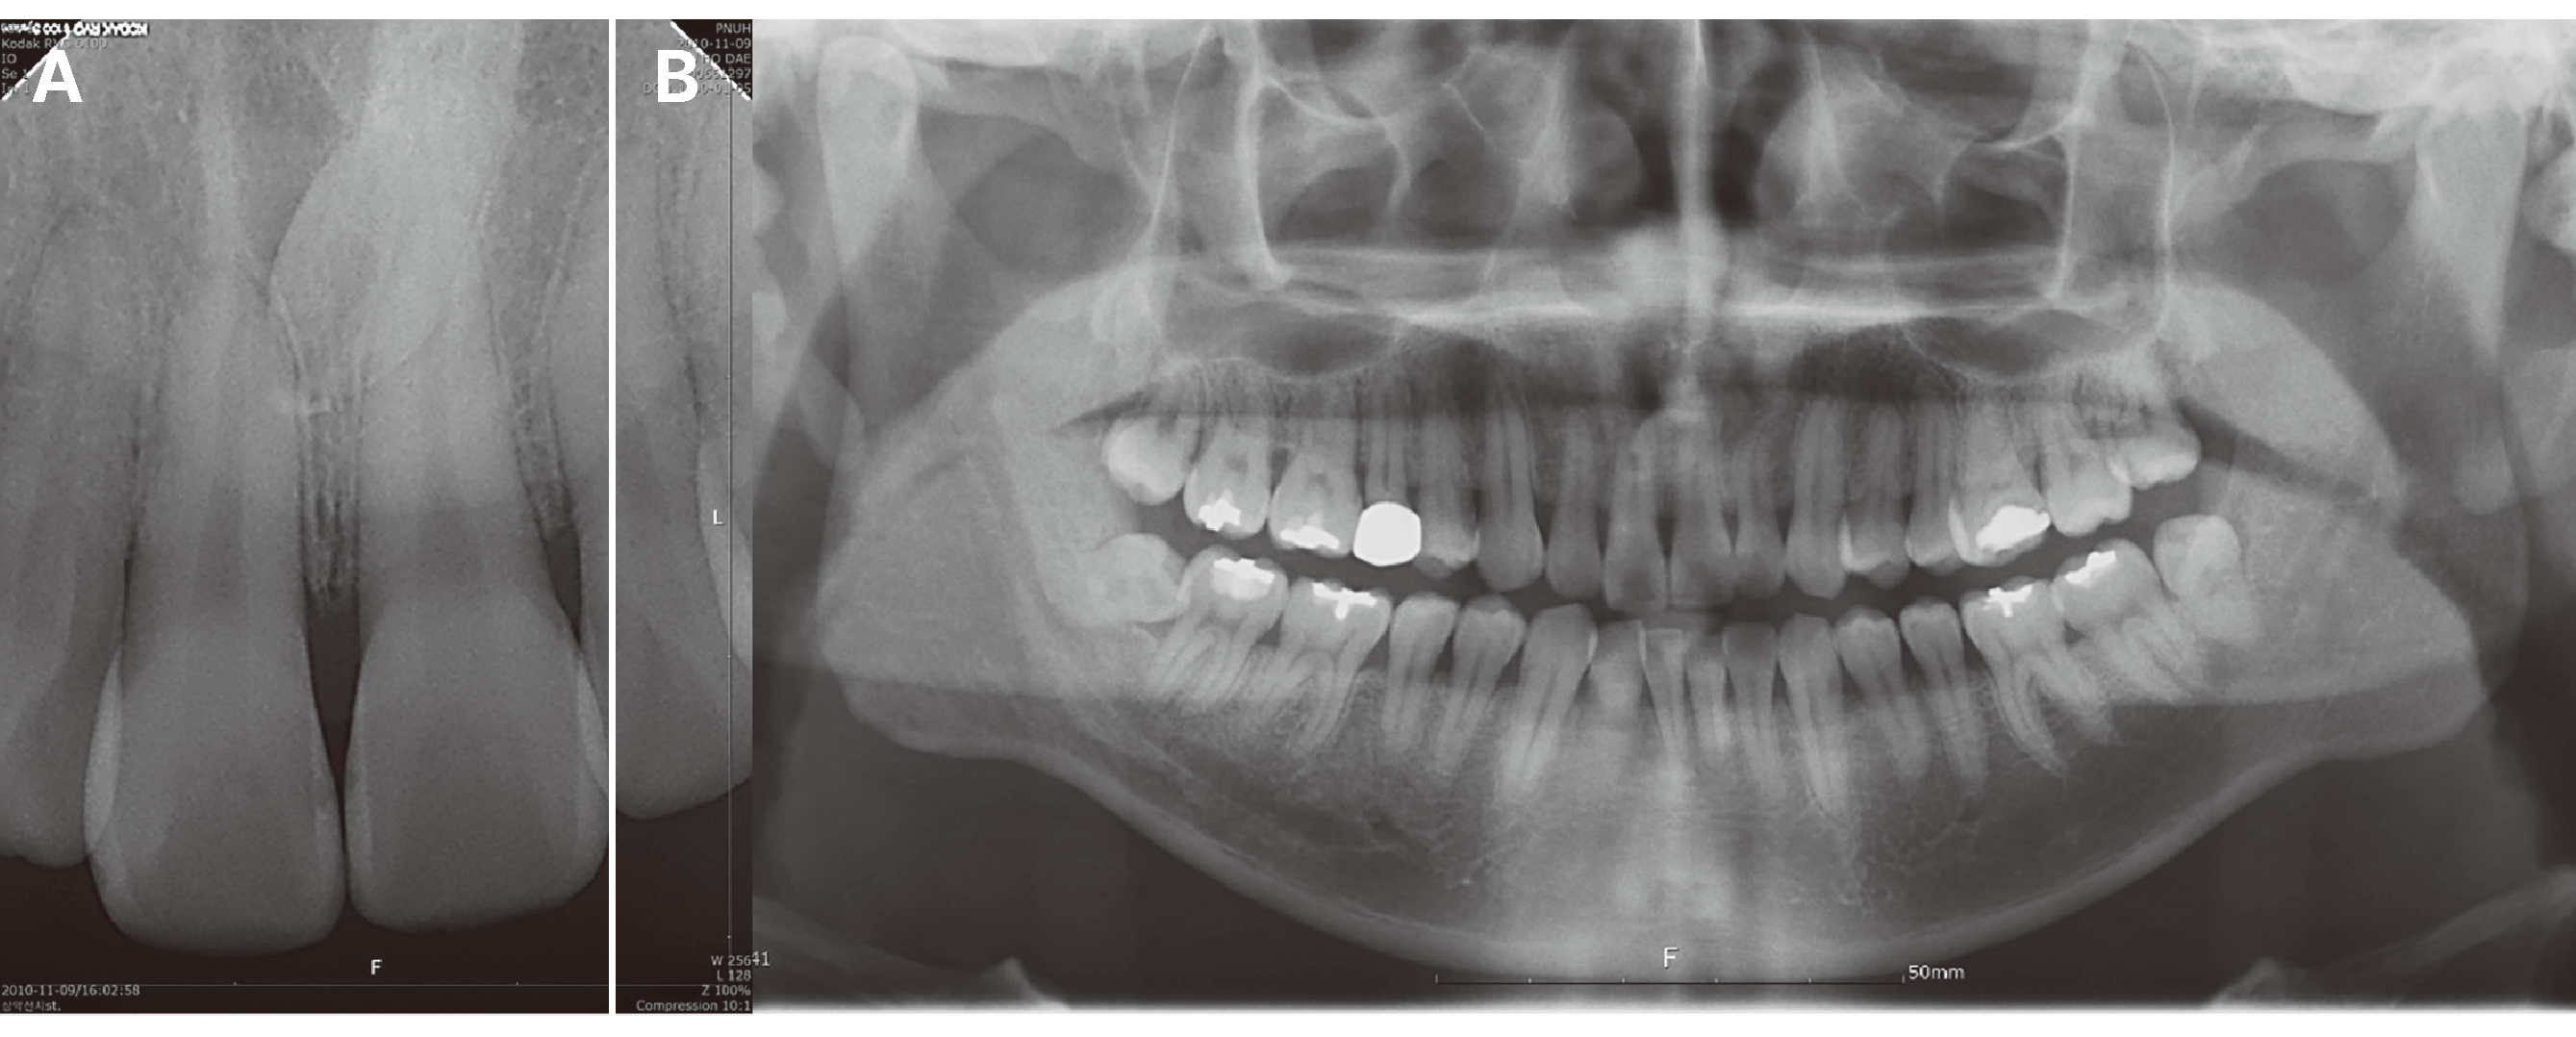

Fig. 5

Clinical presentation of forced eruption and prosthetic restoration (case 3). After periodontal and endodontic treatment (A), preoperative radiography (B), radiography after completion of all the treatment procedures (C), clinical view after treatment completion (D), and after a 2-year follow-up (E). Note the improvement of the intrabony defects and the aesthetic improvement of the soft tissue defect.